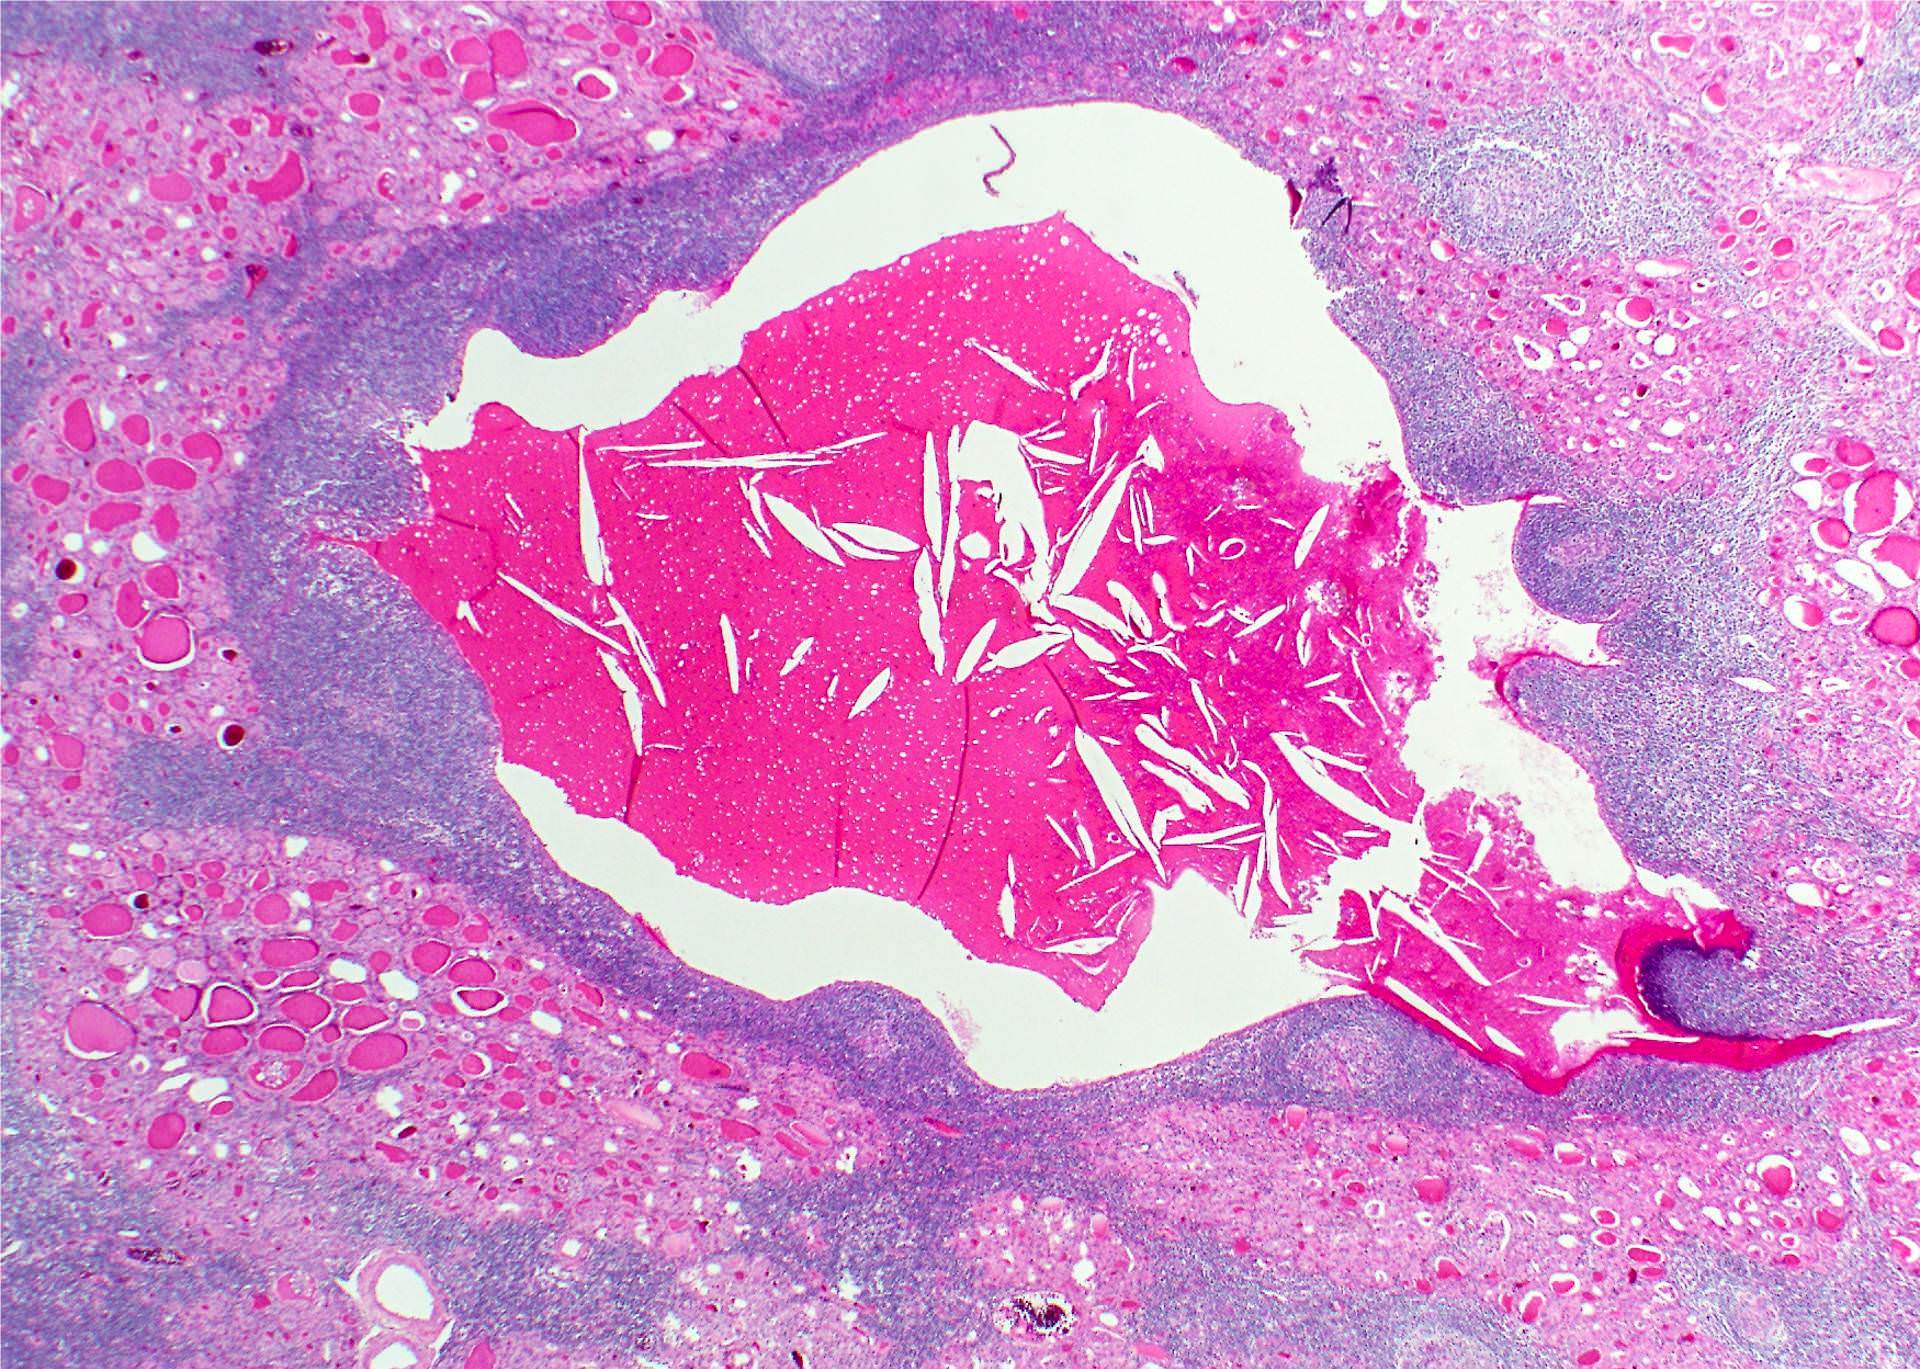

- A smooth walled cyst with mucoid or watery contents, 2 - 6 cm in diameter (up to 10 cm in greatest dimension)

- Infected / ruptured cyst may be obscured or obliterated by the fibroinflammatory reaction; the surrounding soft tissues may be densely fibrotic

- Occasionally found in thyroid tissue as heterotopic cartilage, thymus or solid cell nests representing ultimobranchial body remnants

- Parathyroid glands, thymic tissue, tiny masses of cartilage and tiny glands lined by ciliated cells may be seen in normal thyroid glands, presumably related to anomalies of the development of the branchial pouches (J Anat 1976;122:77)